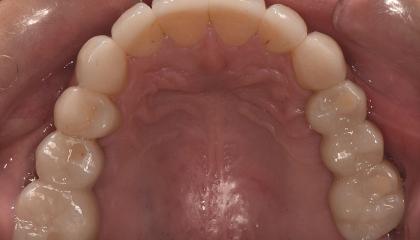

After